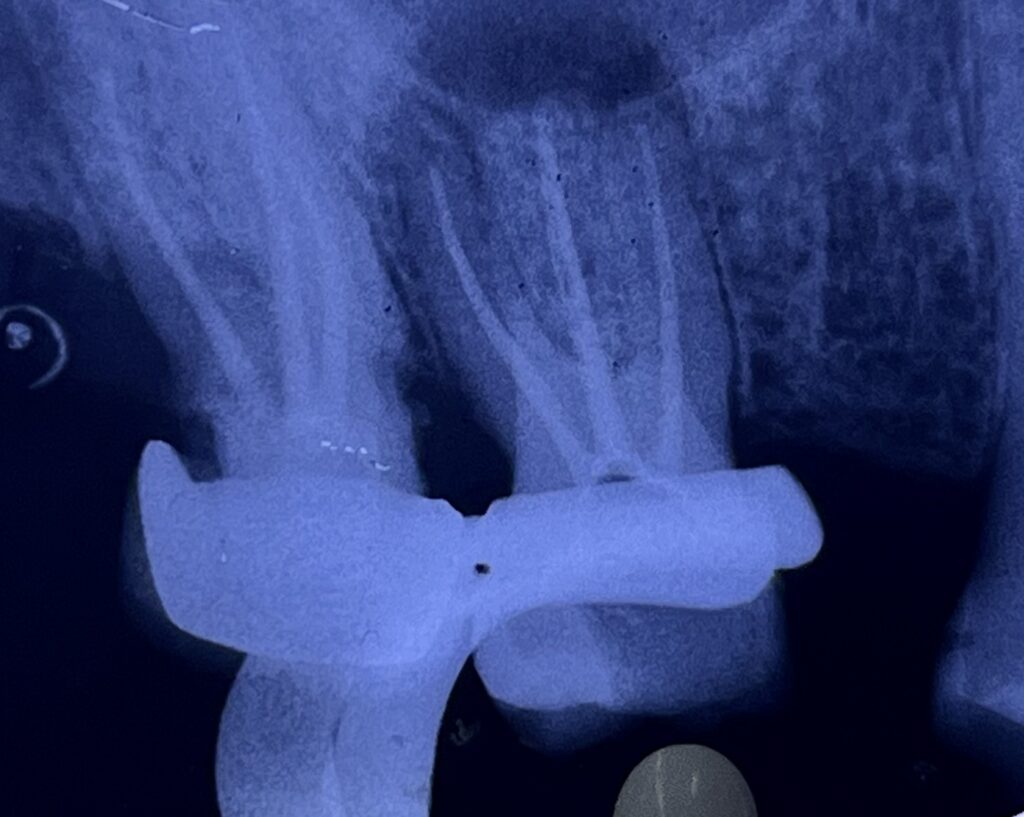

- Endodontically treated posterior tooth

- Moderate to extensive loss of coronal structure

- No signs of acute pathology